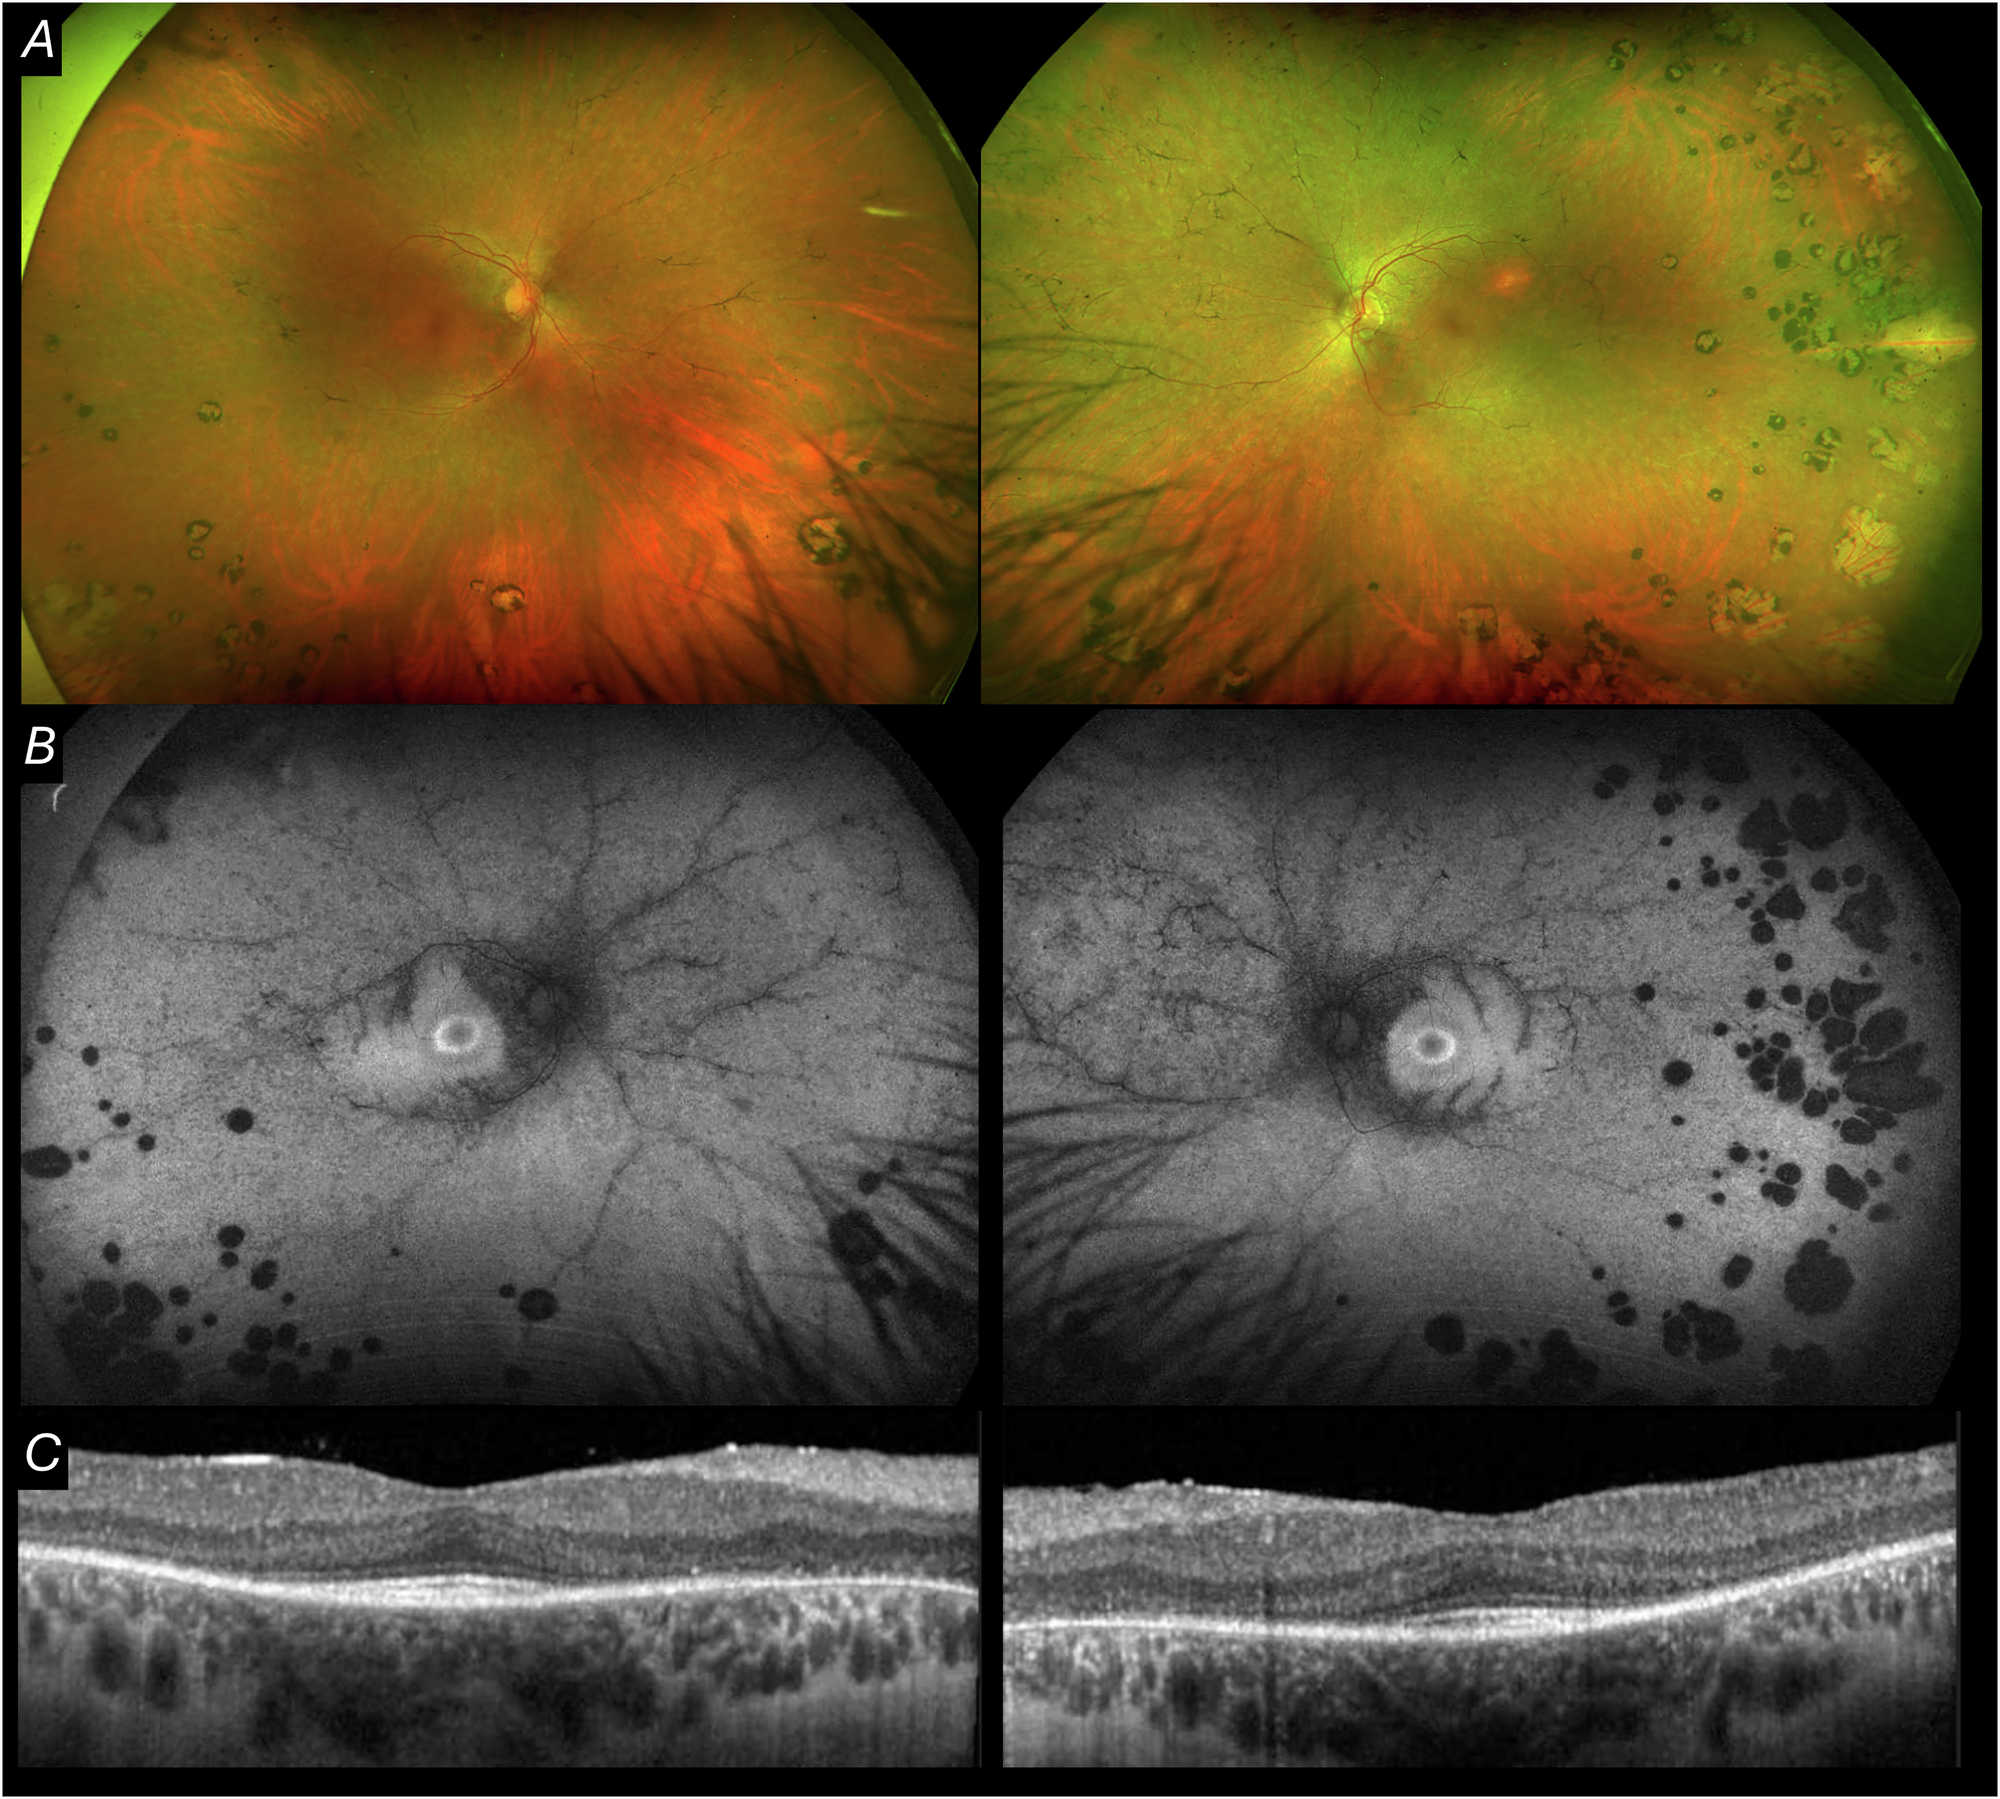

Fig. 4: Multimodal imaging from Case 5.

A Ultra-widefield pseudocolour imaging from both eyes. B Fundus autofluorescence showing characteristic hyperautofluorescent ring (“Robson ring”). C OCT demonstrating outer retinal thinning with preserved fovea from both eyes.